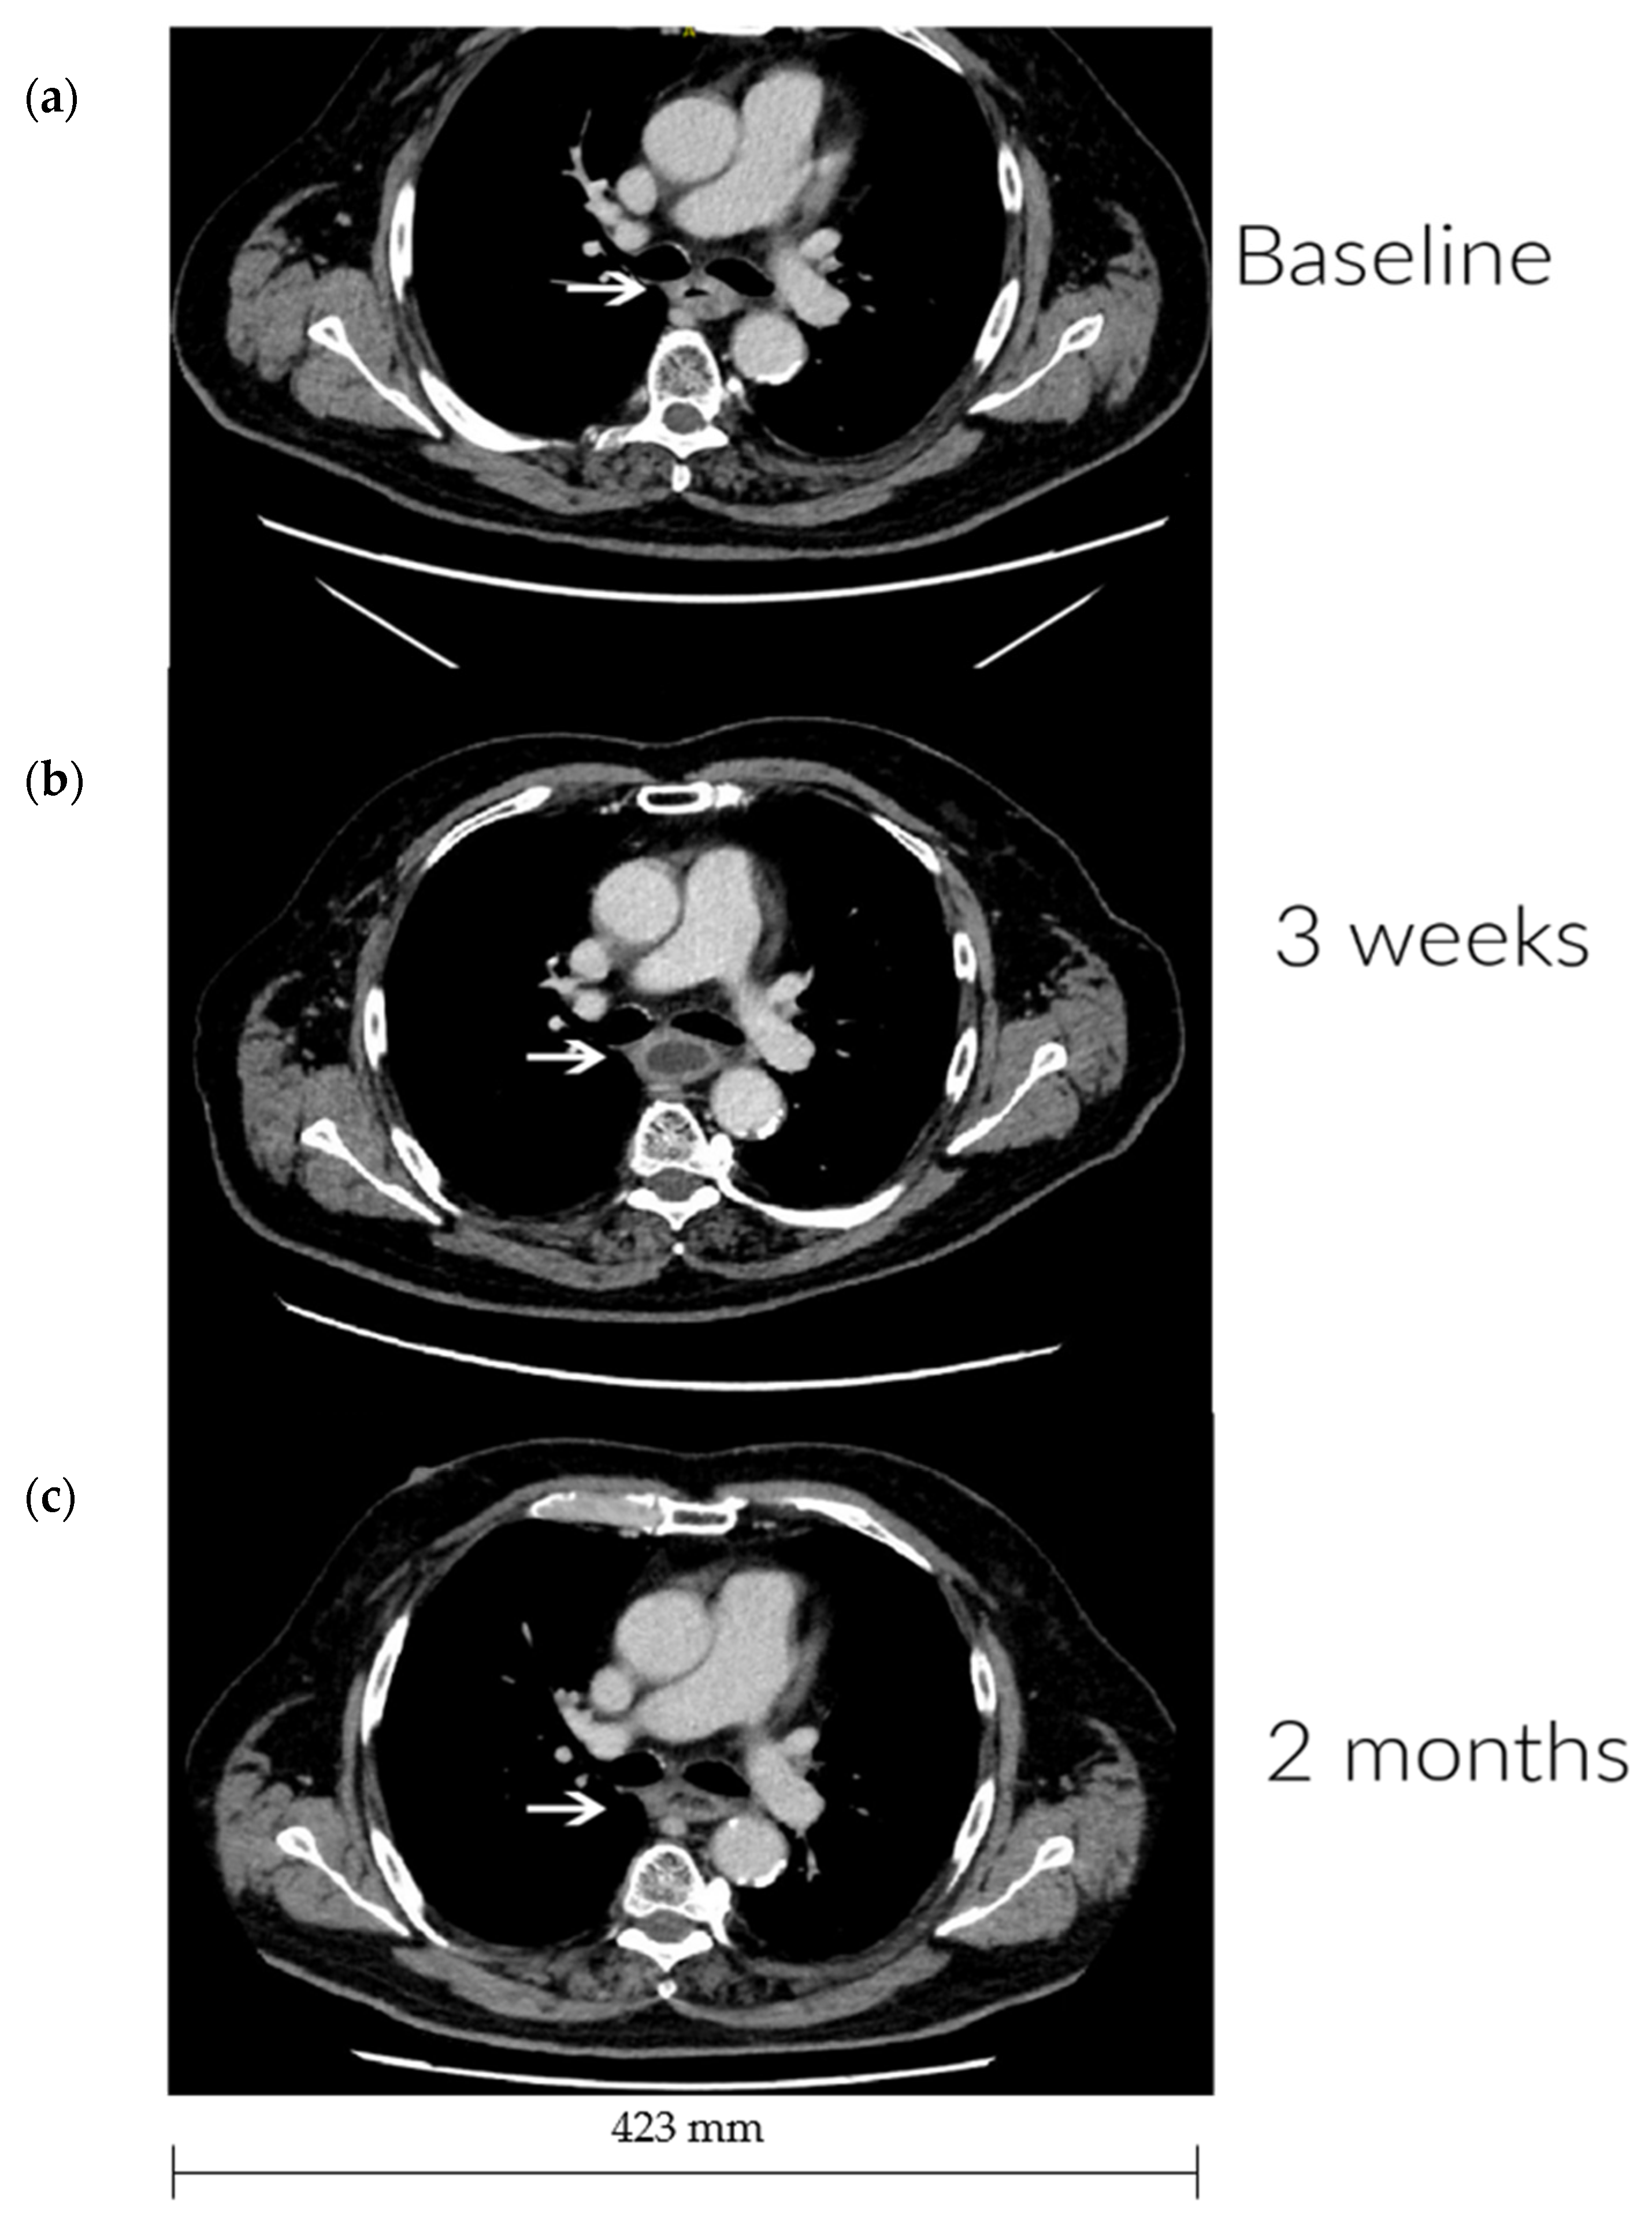

| 7 | - | 0, 0, 0, 1 | 0, 0, 0, 0 | Partial response (2 months) |